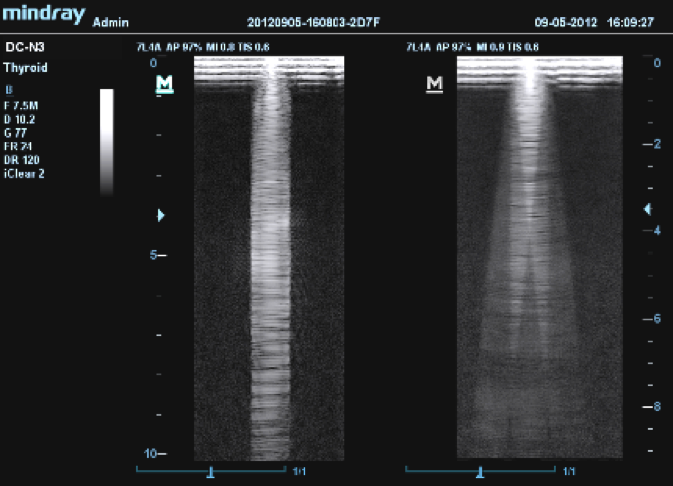

Принцип работы многолучевого составного сканирования (компаундинга) заключается в объединении кадров, полученных при генерации ультразвука под разными углами.

13.png